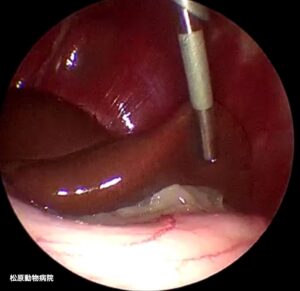

画像:腹腔鏡下肝生検(ラパロ肝生検)の様子

小さな術創からカメラを挿入し、腹腔内で手術を行います。

術創が小さいため、他に合併症や懸念されることがなければ、日帰り手術で対応しています。また、高画質なカメラを肝臓のすぐそばまで到達させることで、肝臓の肉眼所見も詳細に観察することが可能です。